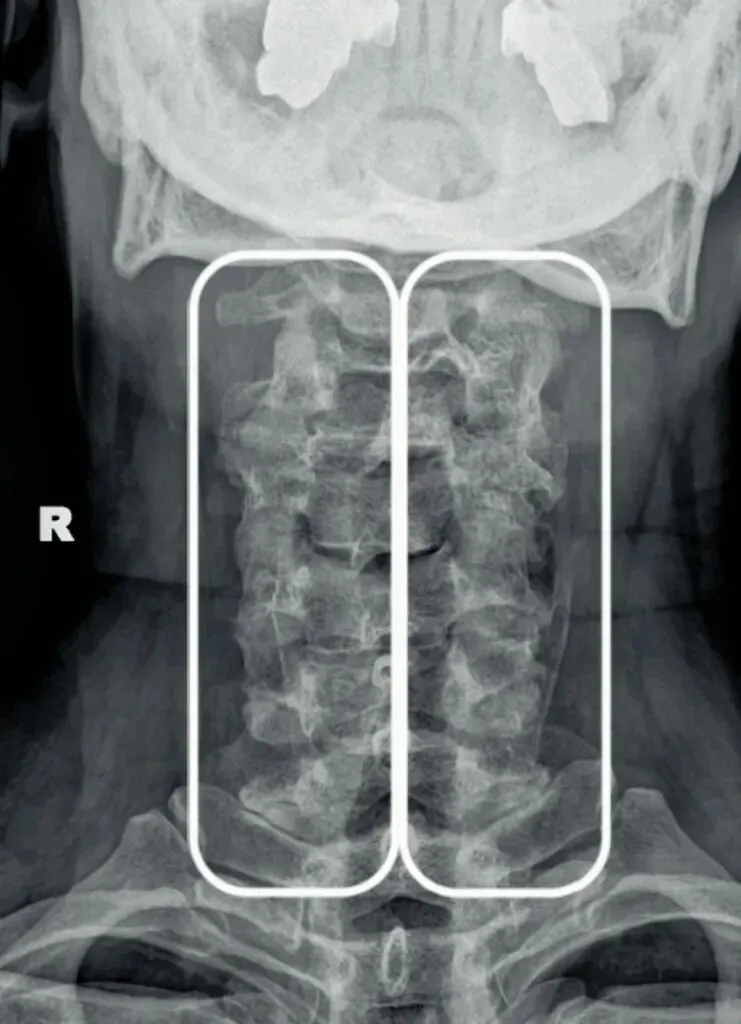

十张口是指寰枢椎的结构和位置关系,我们主要观察寰齿间隙和寰枢关节间隙及寰椎侧块的大小,来判断寰枢关节有无脱位的情况。

首先是寰齿间隙,如果枢椎与颈三的棘突位于同一条直线,

那么寰齿间隙哪边宽,就代表寰椎向哪边发生了侧方移位。

如果不在一条直线上,那就代表枢椎也有侧向的移动或旋转。

接下来是寰枢关节间隙,也称寰枢外侧关节,主要看两侧间隙是否等大,

如果一边宽一边窄,就代表寰椎向窄的一方发生了侧向倾斜。

再下来看寰椎侧块的大小,正常情况下侧块两边的宽度是等大的,

如果哪边侧块变大,就代表哪边的侧块向前方发生了旋转。